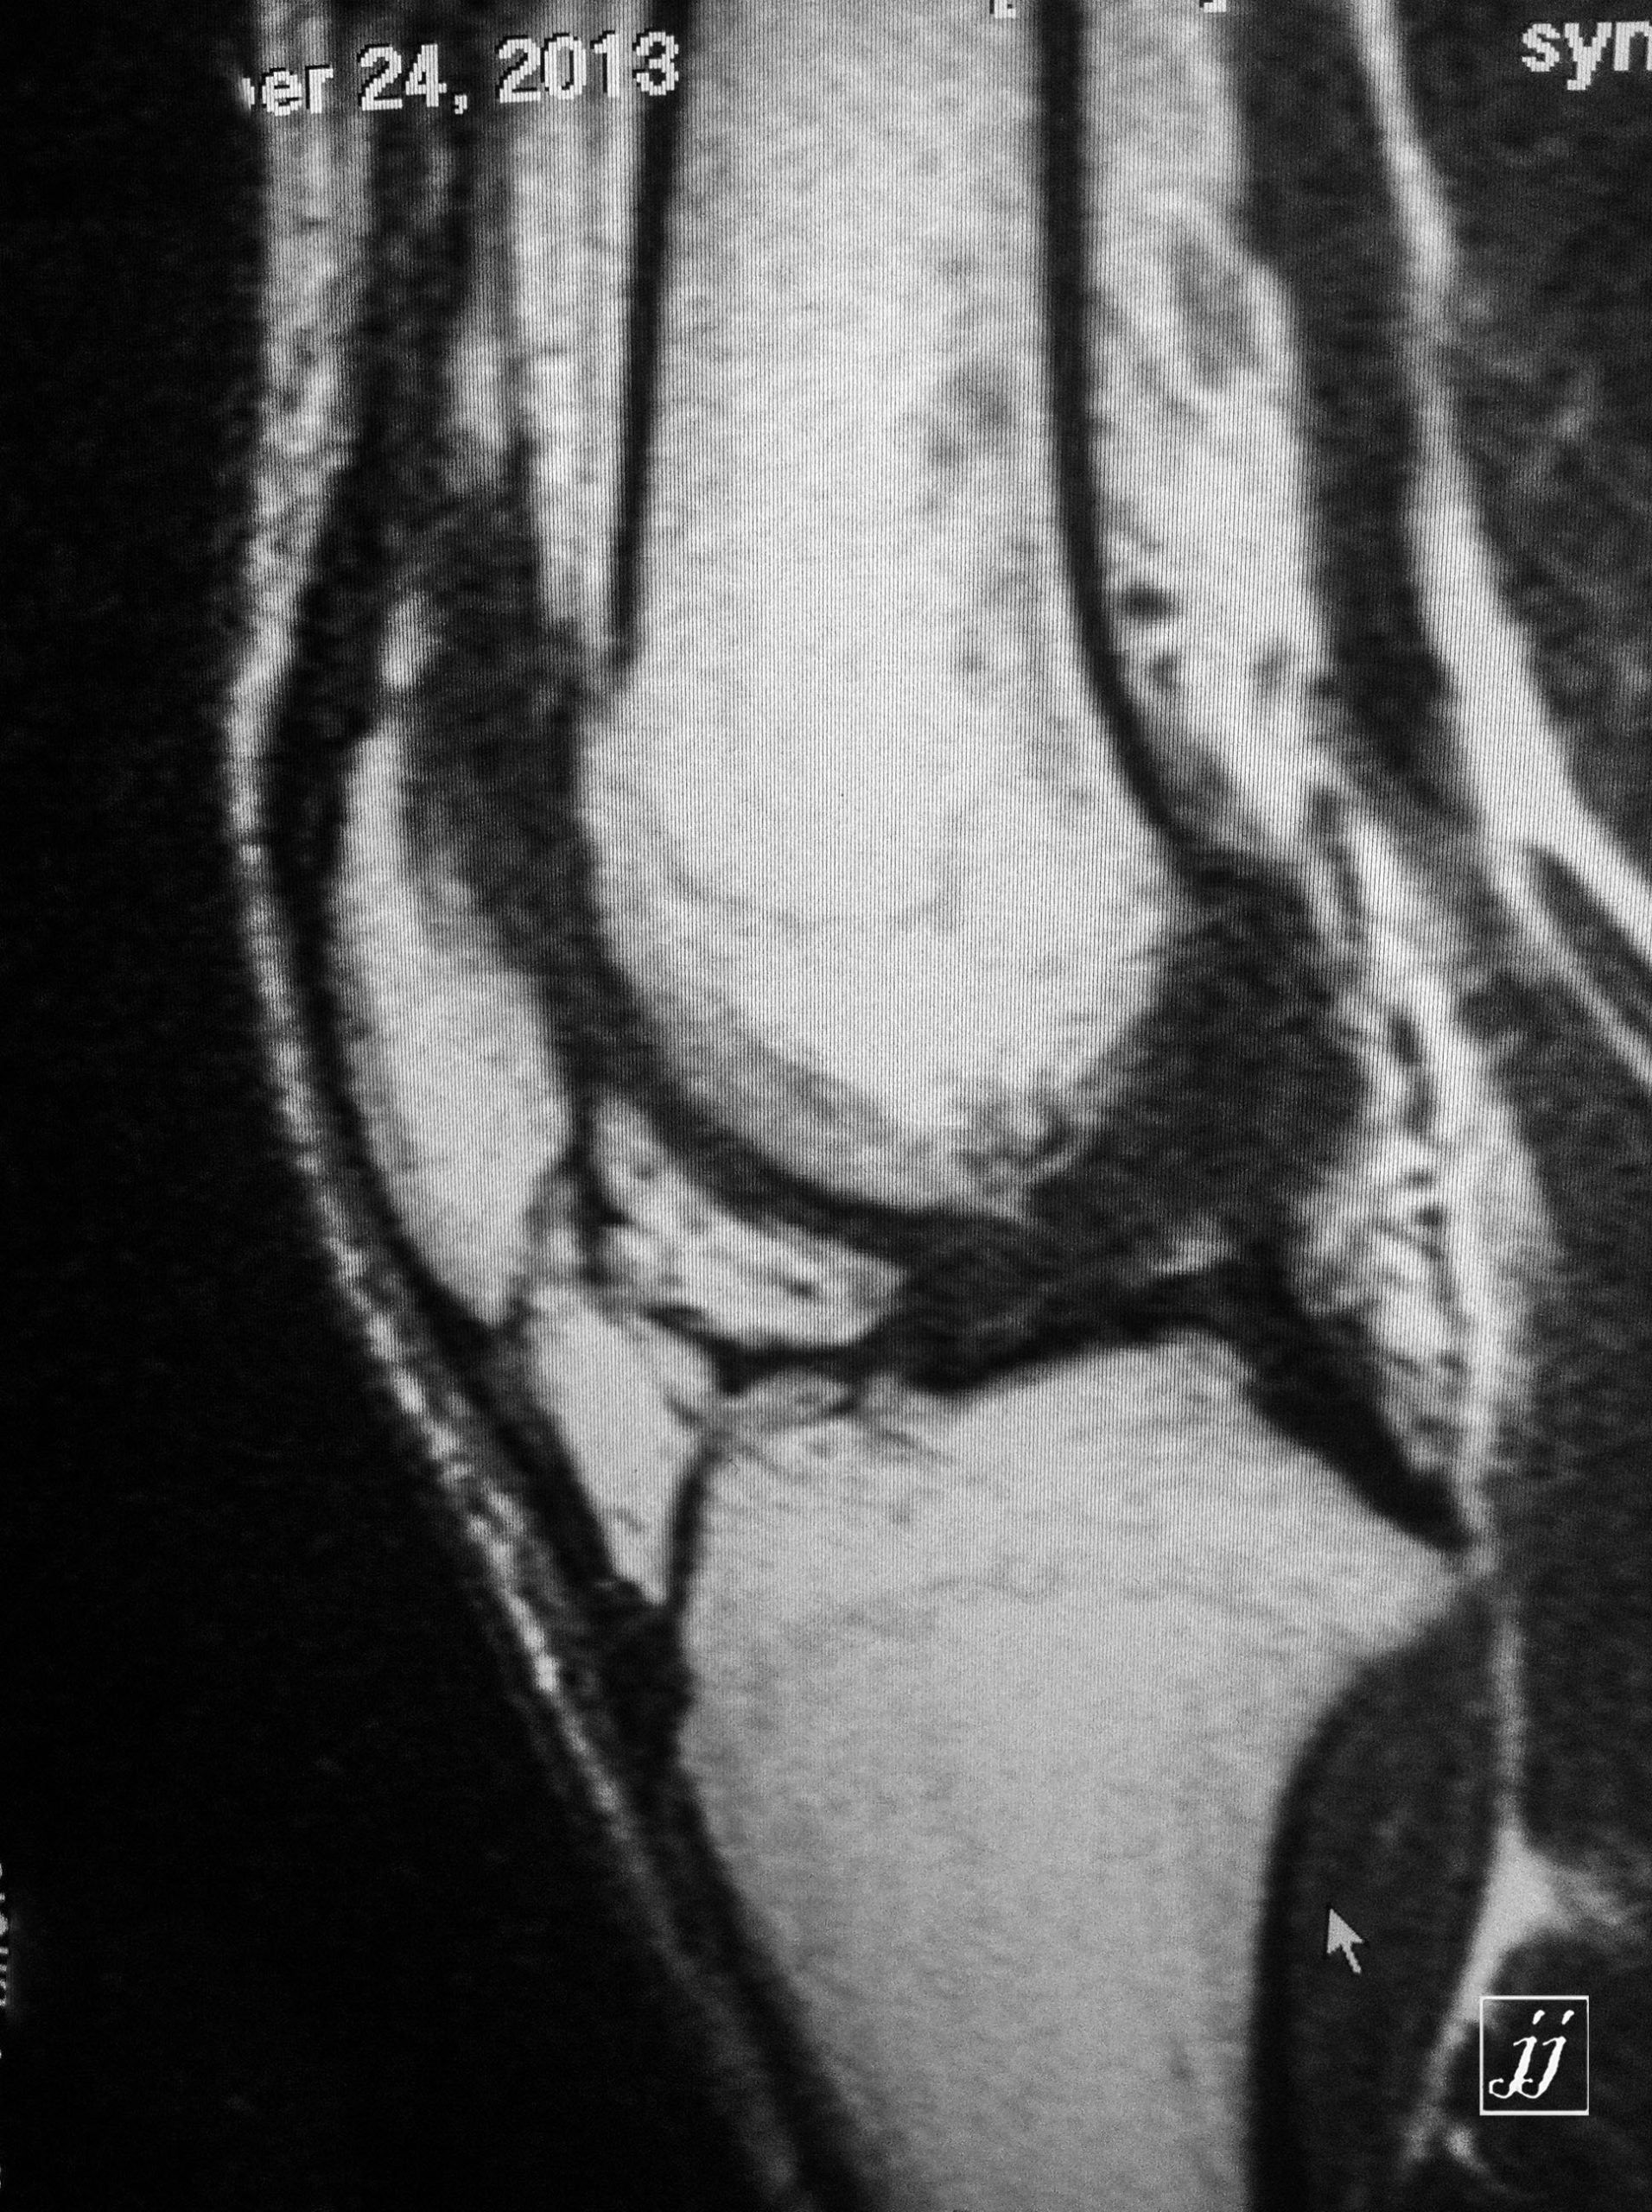

MSK- a medial plica in supra patellar poach (3)